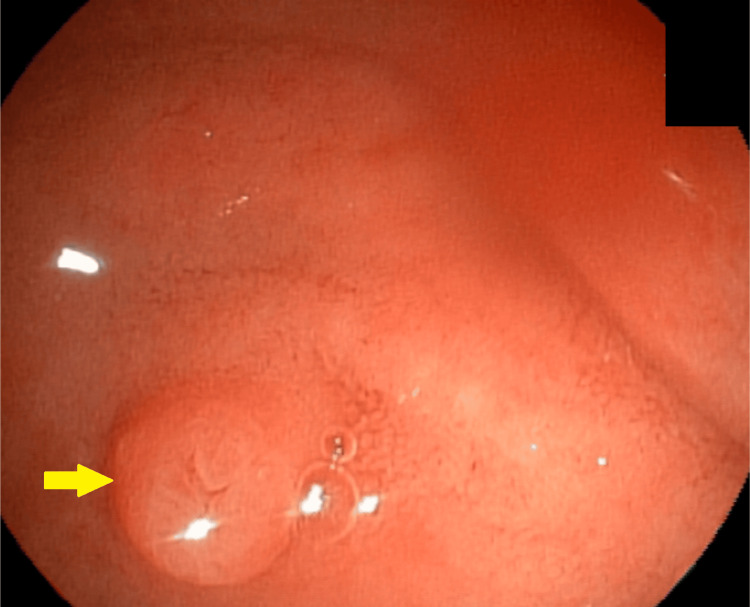

A 34-year-old white female patient with a body mass index (BMI) of 35 presented with right upper quadrant abdominal pain and jaundice, without fever. Imaging studies revealed cholelithiasis and choledocholithiasis. During ERCP, a small papilla of Vater was identified, making cannulation of the common bile duct (CBD) difficult; the guidewire repeatedly entered only the main pancreatic duct. The double-wire cannulation technique was therefore employed, allowing successful access to the bile duct (Figures 1–2).